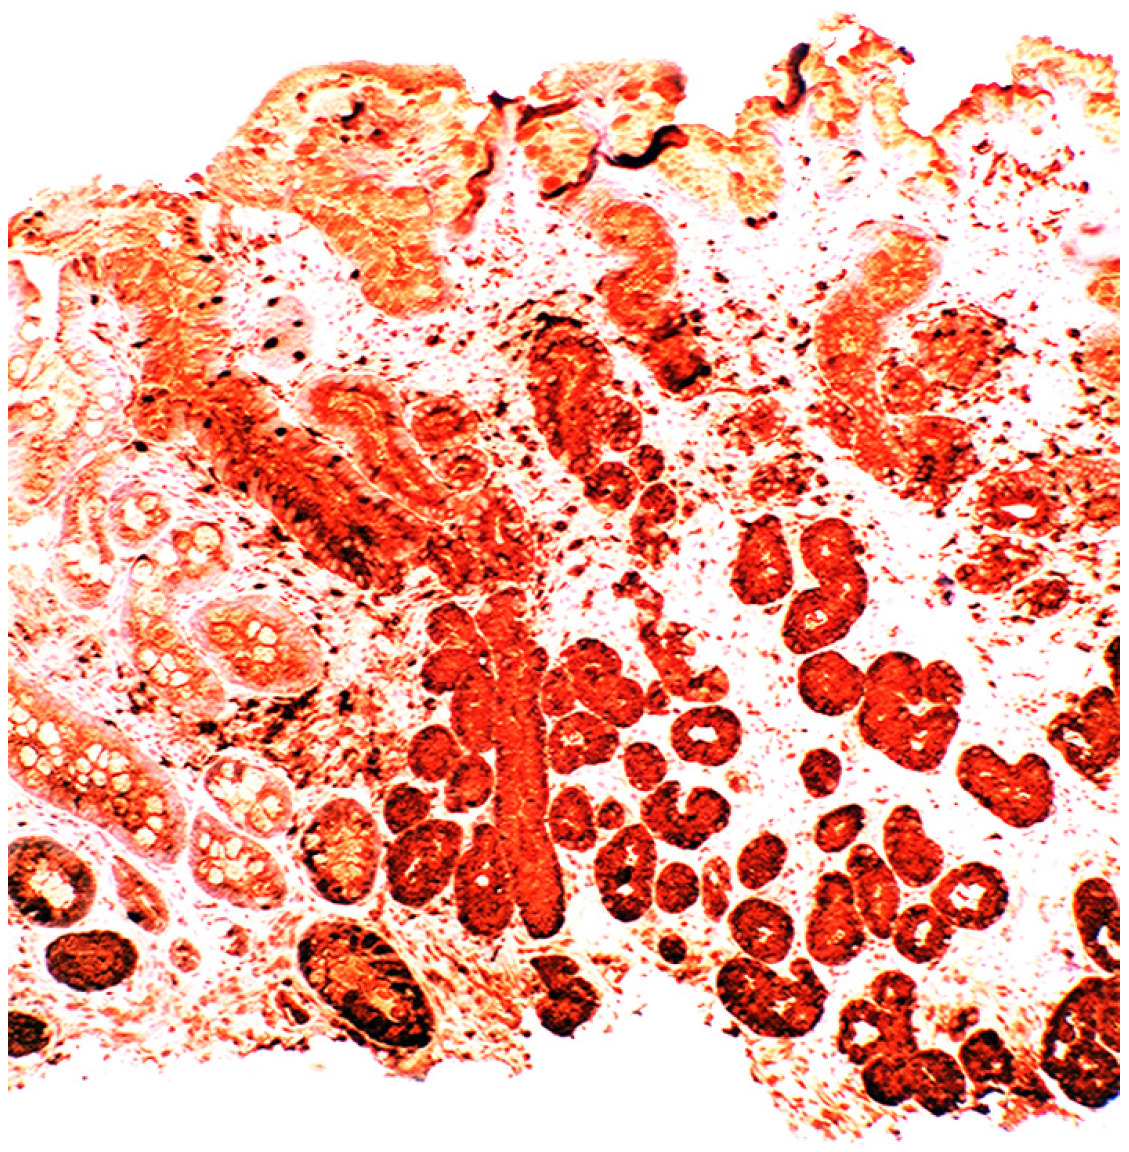

In chronic gastritis lysozyme is up-regulated in the neck region of the oxyntic mucosa, in antral pyloric glands (Figure 5) and in the surface-foveolar epithelium of the oxyntic mucosa [8]. In cases with in intestinal metaplasia, lysozyme is up-regulated in goblet cells (Figure 6), and in Paneth cells. In cases with autoimmune gastritis, lysozyme is up-regulated in pseudo-pyloric glands (Figure 7).

Figure 6.

Chronic gastritis with intestinal metaplasia. Left panel: Oxyntic (corpus) mucosa showing lysozyme expression in goblet cells and in mucus neck cells. Note absence of lysoyme expression in parietal cells in the lower part of the picture (below arrows); Right panel: Antro-pyloric mucosa showing lysozyme expression in goblet cells and in Paneth cells at the bottom of the crypts (arrows, lysozyme immunostain, ×10).